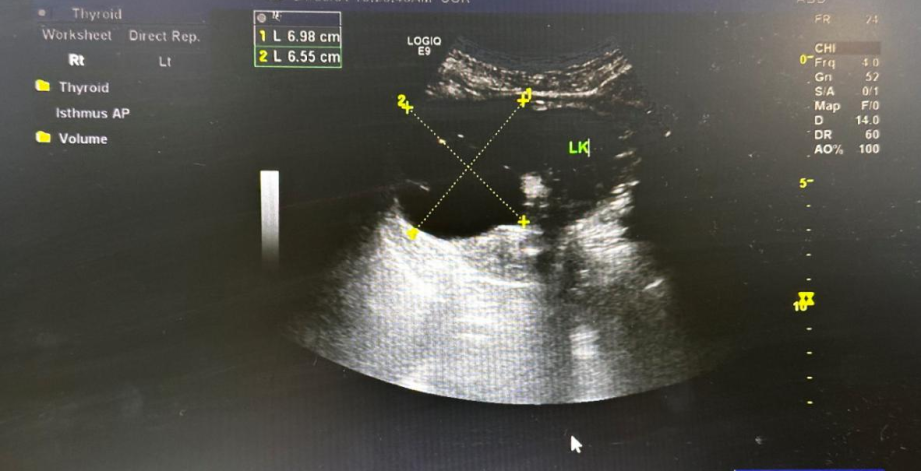

患者,男,73岁,发现双肾囊肿半年余,患者半年前体检发现泌尿系彩超,双肾囊肿,左肾囊肿大小6.4✖4.5✖5.5cm,2024年6月4日就诊我科门诊复查泌尿系彩超示:双肾囊肿,左肾囊肿大小7.2✖6.0✖5.5cm。2024年6月18日为行肾囊肿穿刺引流硬化治疗入院。初步诊断:双肾单纯性肾囊肿。

术前超声图片